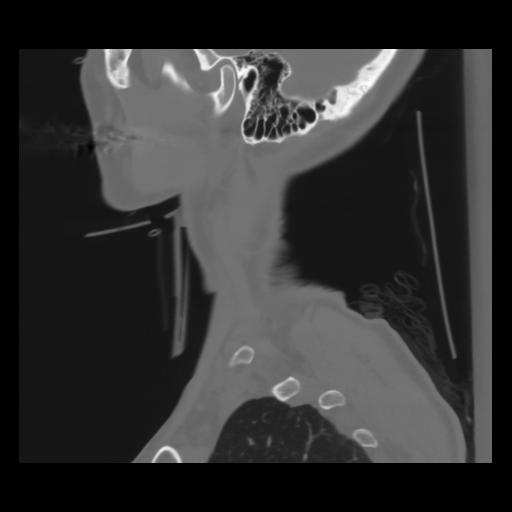

14 P.BLANDAS,,Sagittal,2.000,P.BLANDAS,Sagittal,